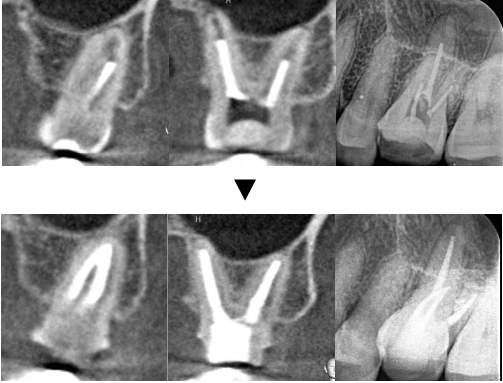

術後12ヶ月

元々根の先の骨吸収はありませんでしたが、術後12ヶ月のCT・レントゲン写真でも病的な所見は認められず、経過良好です。